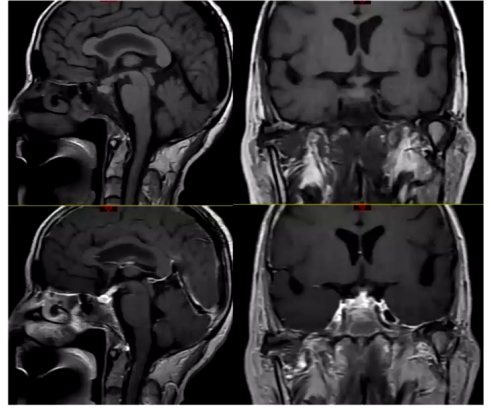

外院头颅MRI:检查显示,9月23日平扫见鞍区及鞍上占位性病变;9月25日增强扫描见垂体区葫芦样异常信号,强化明显,大小约1.9cm×1cm,视交叉略增粗,垂体柄居中,考虑鞍区占位,初步考虑垂体瘤。

治疗第4天,患者入量2850ml,出量1850ml,血钠126.7mmol/L,血钾4.01mmol/L,BNP降低。考虑到患者在糖皮质激素治疗后出现中枢性尿崩症,进一步进行垂体影像学检查,结果显示垂体窝巨大占位较前显著缩小,垂体右缘考虑垂体微腺瘤,神经垂体未见异常,垂体柄增粗并强化,组织细胞增生症待排。

自身免疫性垂体炎(autoimmune hypophysitis,AH)是一种自身免疫介导的罕见疾病,侵犯下丘脑垂体及其邻近器官,分为原发性和继发性。主要表现为腺垂体功能减退、中枢性尿崩症,甚至下丘脑功能障碍。疑诊特点包括头痛、视力下降、视野缺损、中枢性尿崩症、部分或全部腺垂体功能减退,影像学表现为垂体和垂体柄对称性匀称性增大,强化均匀,垂体柄增粗无偏移,垂体后叶高信号消失,视交叉受压移位等。多数患者为孕期或产后女性,继发性患者可能自身抗体阳性或伴有其他自身免疫疾病。需与垂体腺瘤、颅咽管瘤等鉴别,诊断金标准为组织病理学检查,但多通过临床表现、内分泌功能、影像学及糖皮质激素试验性治疗综合诊断。